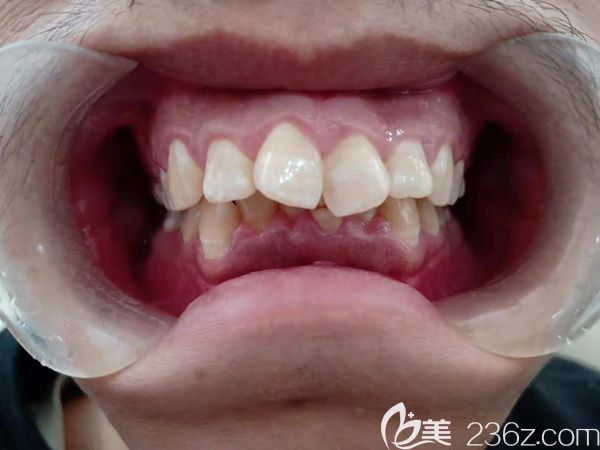

男朋友牙齒太難看,分享和他去廣州陽(yáng)光樹口腔做門牙齙牙深覆蓋矯正后臉型變化圖 b1557 G0 V0

男朋友牙齒太難看了,給大家分享下他在廣州陽(yáng)光樹口腔做門牙齙牙矯正+牙齒排列不齊的深覆蓋臉型變化圖,快來看看他現(xiàn)在變成什么樣了。